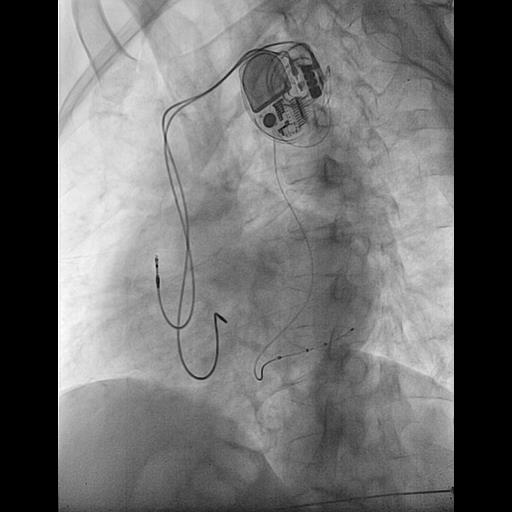

@ShaojieChen1 @hrs_journal @dredcronin @TJaredBunch @d_changy @DanielPMorin @drrakeshg1 @Maeskander @senthil_dorai @DrRoderickTung @pjsm83 @mencardio @ZS279 @clementy_ep @MBergonti @Anand_Ganesan1 @RawahiAl @javadm20 @rdschaller @SchakrabartiEP @EJSMD @LaredoMikael @ugurcanpolatmd @ChiaraValeriano @MDerndorfer @ecgrhythms @adribaran @Basalus @jvillacastin @DrGregMichaud nsHBP, sHBP, LVSP, sLBBP, nsLBBP, LBBAP, LVSP, RVSP, nsRBBP, sRBBP, what should we look forward to next?